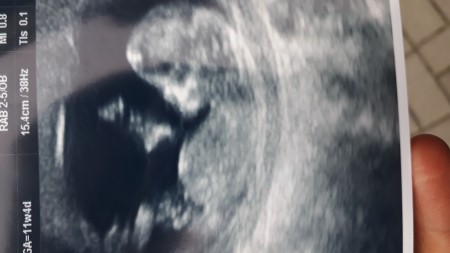

Sizce kız mi erkek mi

Gebelik haftası 11 3 günlük

Erkek benimkide aynı böyleydi :)

Allah bağışlasın canmm ama emin ol erkek hatta belli bak çıkıntı var :)

Aynı görüntü bendede var doktor o zamanlar banada erkeğe benziyor demişti net bişey demedi eve geldim dedim bu erkek bu çıkıntı var bak diye eşime gerçektende erkek çıktı belli oluyor sağlıklı olsunlarda erkek kız farketmiyor